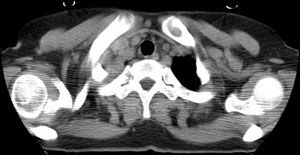

女性,30岁。

病史为胸痛20多天,无畏寒发热,无消瘦,无咳嗽咳痰。总之症状很逍遥。

2.肺ct表现为两肺多发大小不等结节影,大结节位于肺尖部,小结节多位于肺外带胸膜下,大结节内可见支气管充气征,周围可见月晕征(指在结节状或肉芽肿样病灶周围呈环形磨玻璃影),右肺门及腔静脉后可见小淋巴结,右侧胸腔内少量液体。

两肺散在分布大小不等的肿块及结节影,边缘毛糙,有分叶、毛刺,病灶密度不均匀,可见支气管充气相与空泡征。病变大多位于胸膜下,可见胸膜凹陷及胸腔积液。气管腔静脉间可见小结节影。